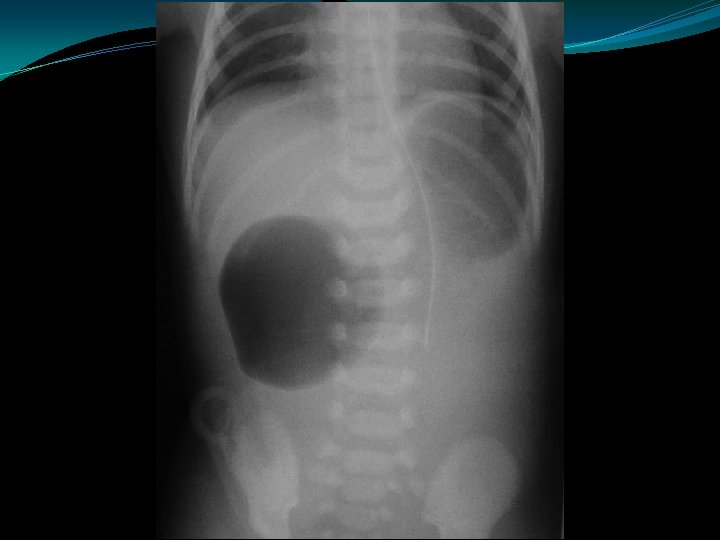

Meconium Ileus �Usually a manifestation of cystic fibrosis � 20% of infants with CF present with mec ileus �Obstruction of proximal ileum by thick, sticky round meconium pellets �Absence of air fluid levels �“soap bubbles” �Complications: �perforation, peritonitis, pseudocyst, ileal atresia/stenosis

Meconium Ileus �Contrast enema: �Small colon �Filled with pellet-like meconium when contrast extends to IC valve �Contrast can wash out the obstructing plugs and meconium plugs �The diagnosis of CF should be ruled-out